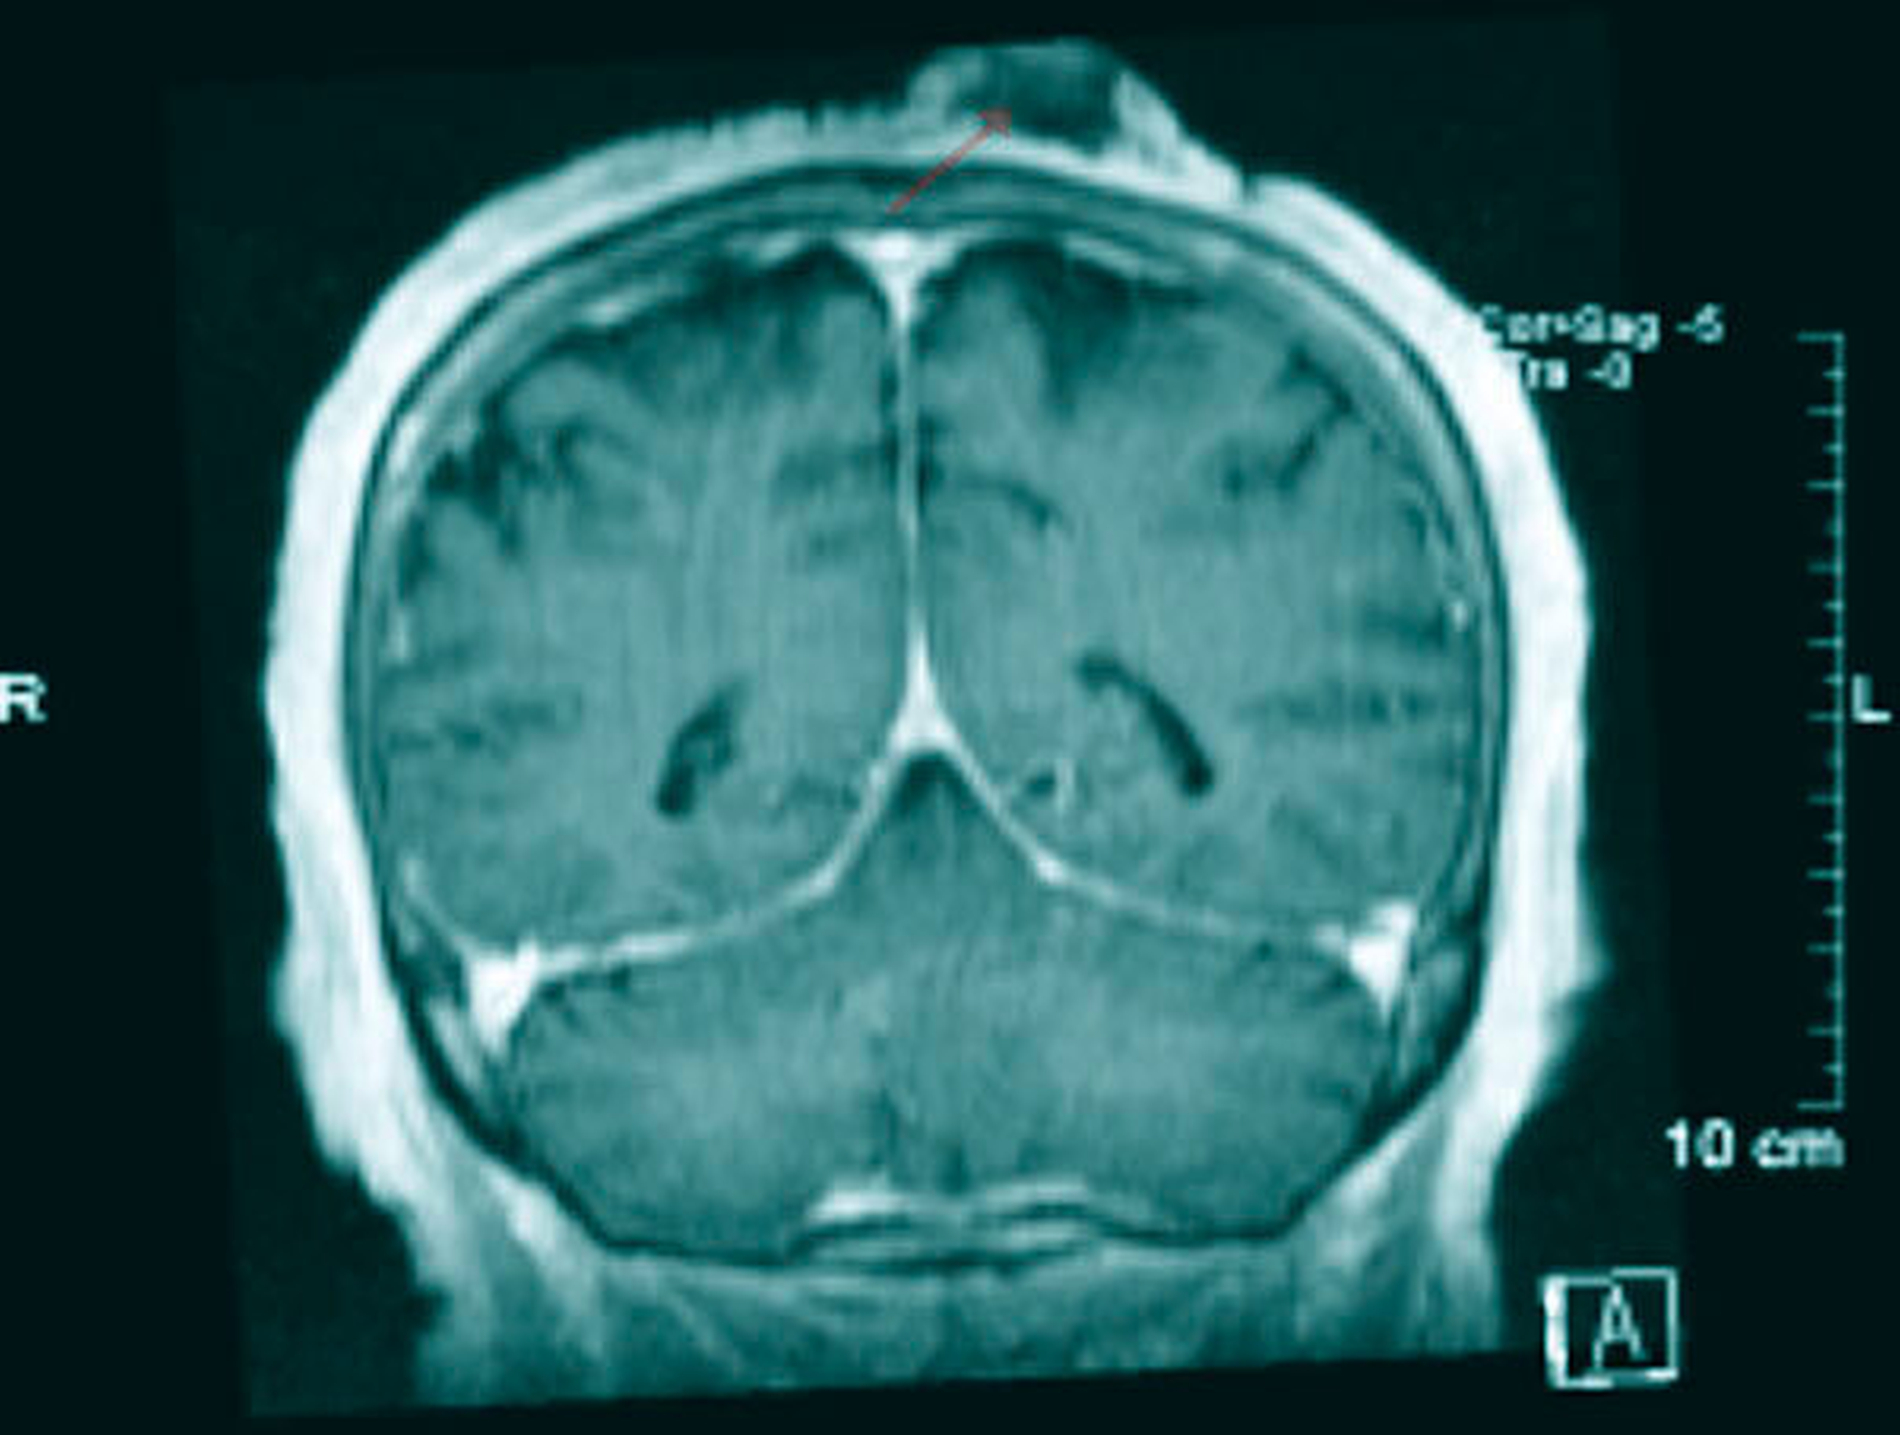

Im MRT zeigte sich eine occipital gelegene, ausgedehnte Raumforderung (Abbildung 4), die im PET-CT zum komplementierenden Staging mit einem Standard-FDG-Uptake (SUVmax) von 19.4 bestätigt wurde. Es ergaben sich keinerlei Hinweise für eine lokoregionäre Metastasierung, Fernmetastasen oder einen Zweittumor (Abbildung 5).